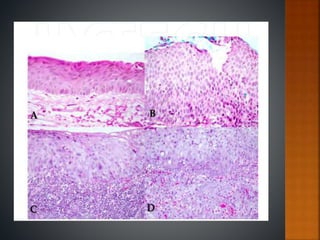

 Histopathological evaluation of the lesion

following incisional & excisional biopsy.